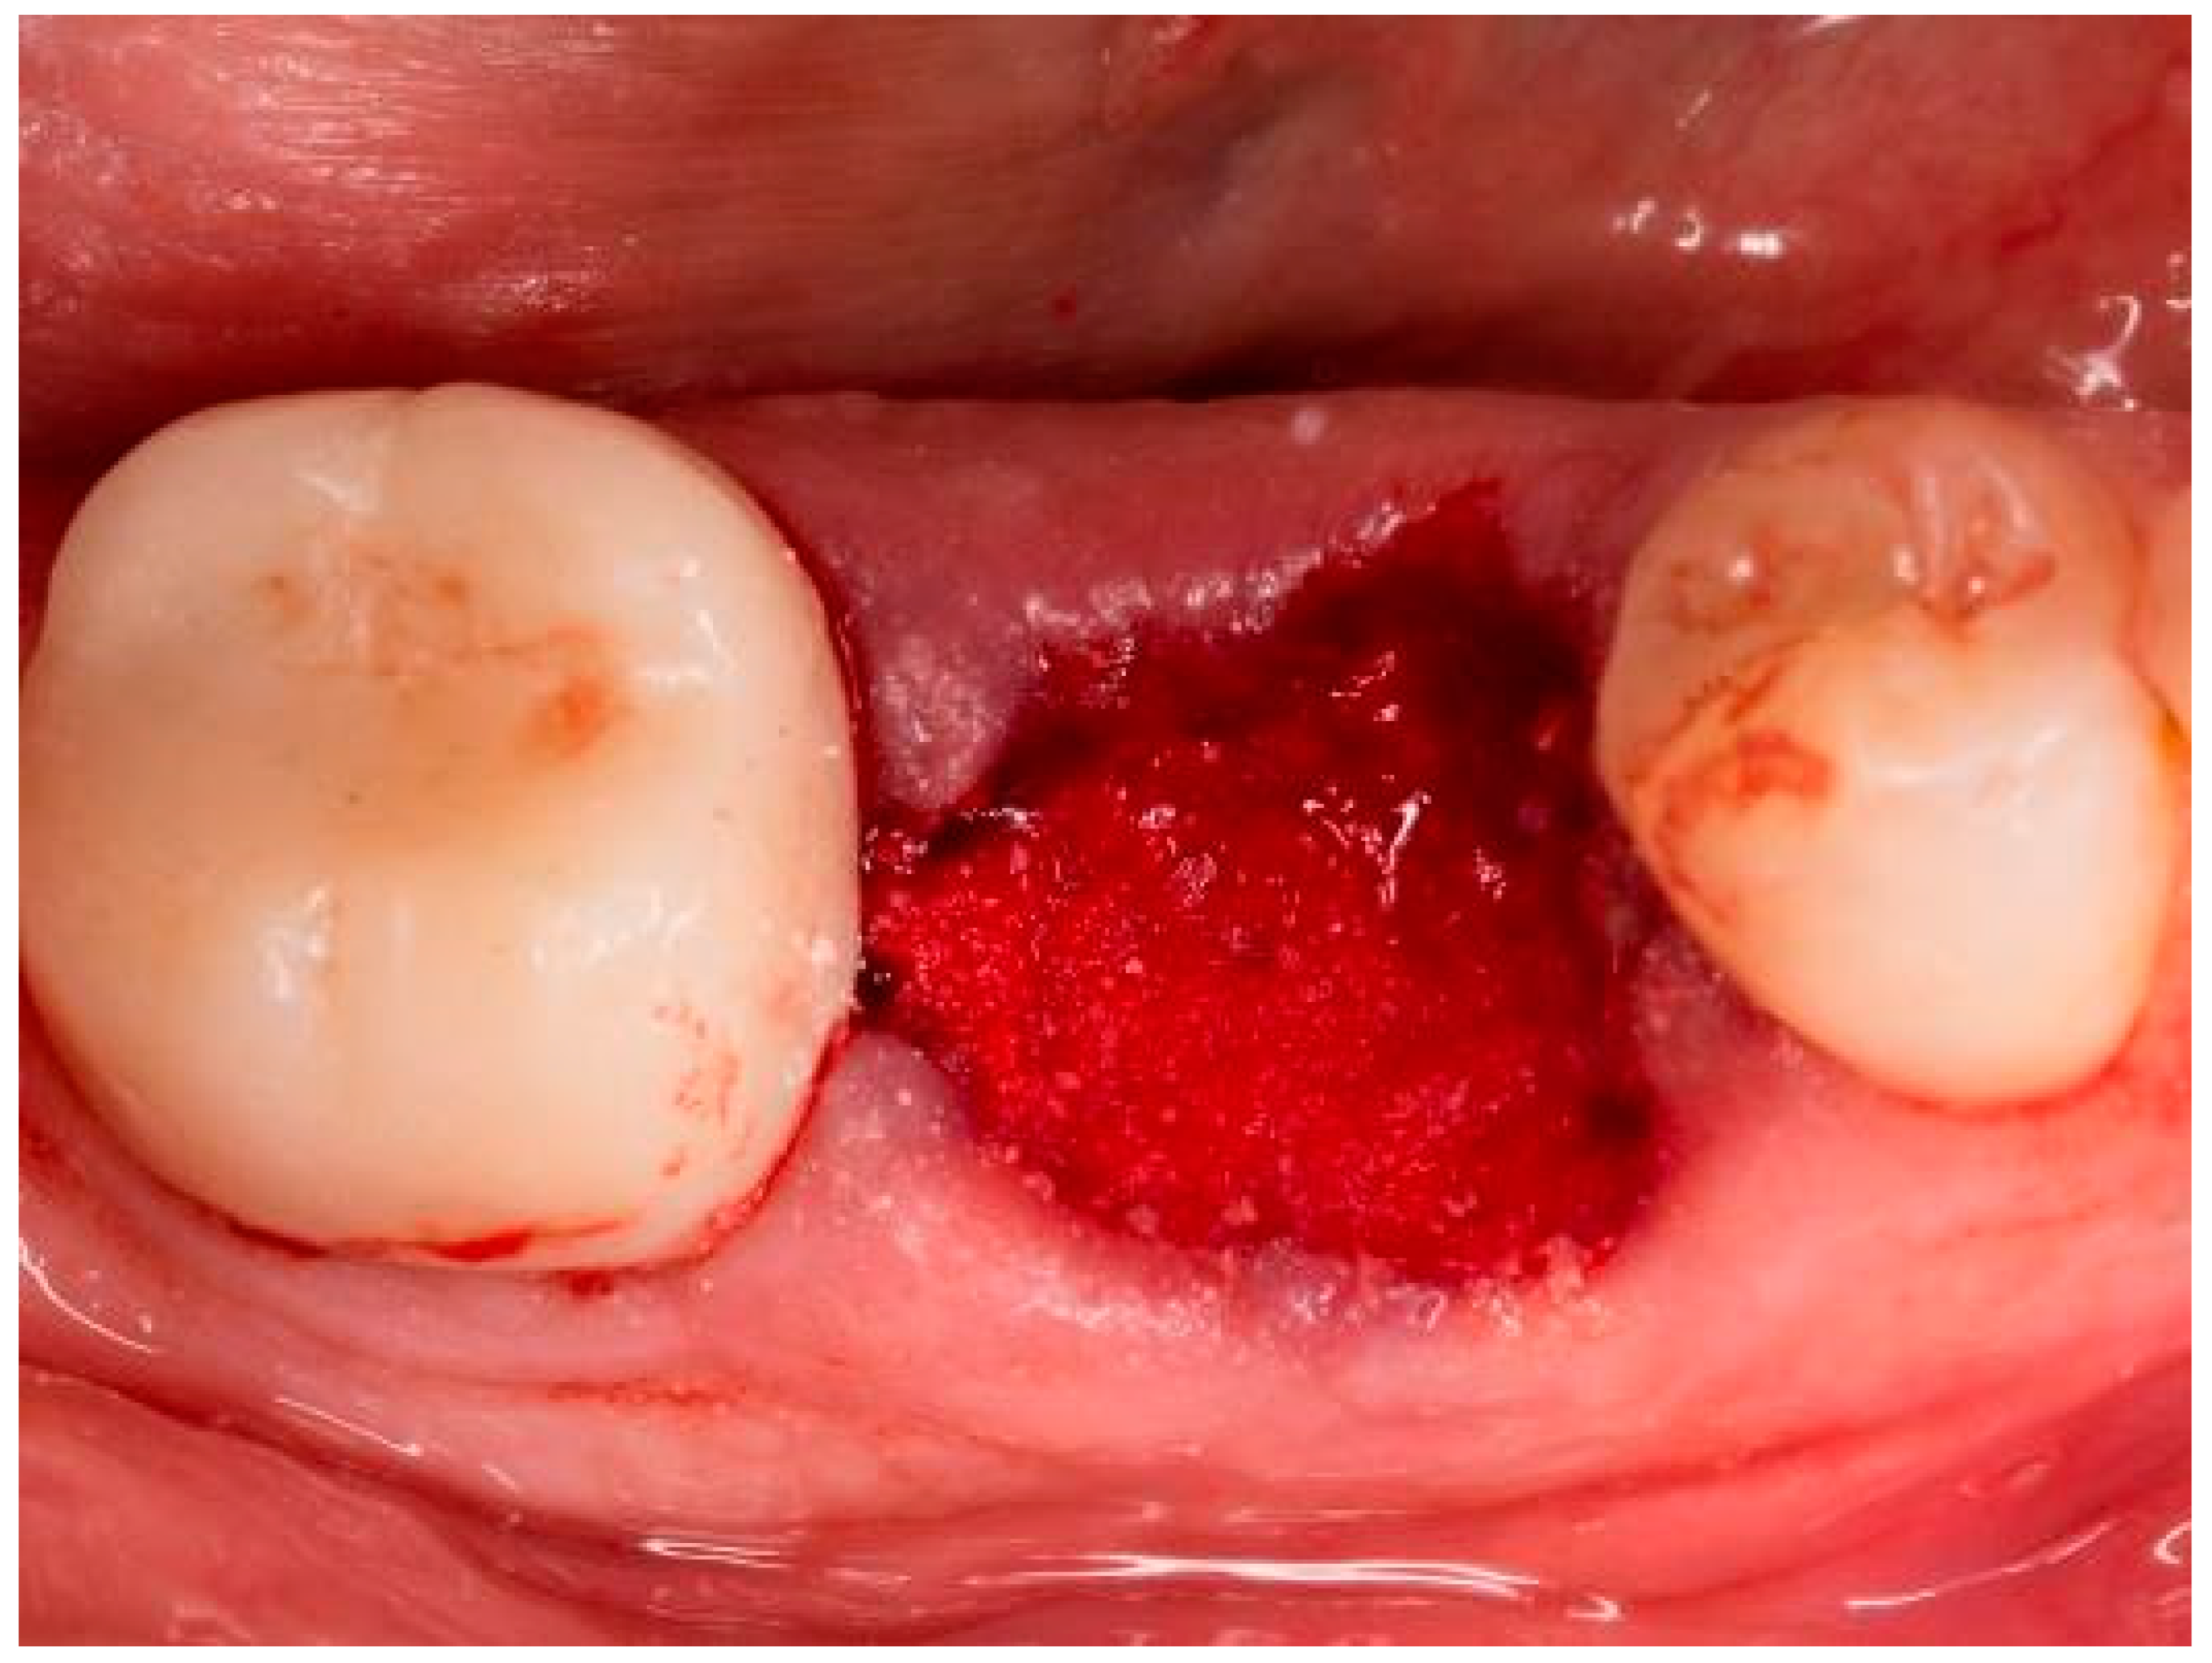

| Case No. | Sex | Age | Regio (FDA): | Reason for Tooth Loss: | Integration Period of the Graft: | Smoking Behavior: | General Medical History: |

|---|---|---|---|---|---|---|---|

| 1 | m | 42 | 25 | fracture | 130 | never | no abnormal medical history |

| 2 | m | 63 | 17 | endodontic | 319 | 10 cig./d | no abnormal medical history |

| 3 | m | 45 | 25 | unrestorable | 133 | never | no abnormal medical history |

| 4 | f | 77 | 36 | fracture | 207 | former smoker | type 2 diabetes, medicated |

| 5 | f | 62 | 46 | endodontic | 190 | never | no abnormal medical history |

| 6 | m | 54 | 37 | endodontic | 253 | former smoker | type 2 diabetes, medicated |

| 7 | m | 55 | 37 | tooth tilting | 292 | never | atopic individual |

| 8 | f | 43 | 26 | endodontic | 187 | former smoker | no abnormal medical history |

| 9 | m | 45 | 25 | unrestorable | 146 | former smoker | atopic individual |

| 10 | f | 44 | 15 | endodontic | 184 | never | no abnormal medical history |